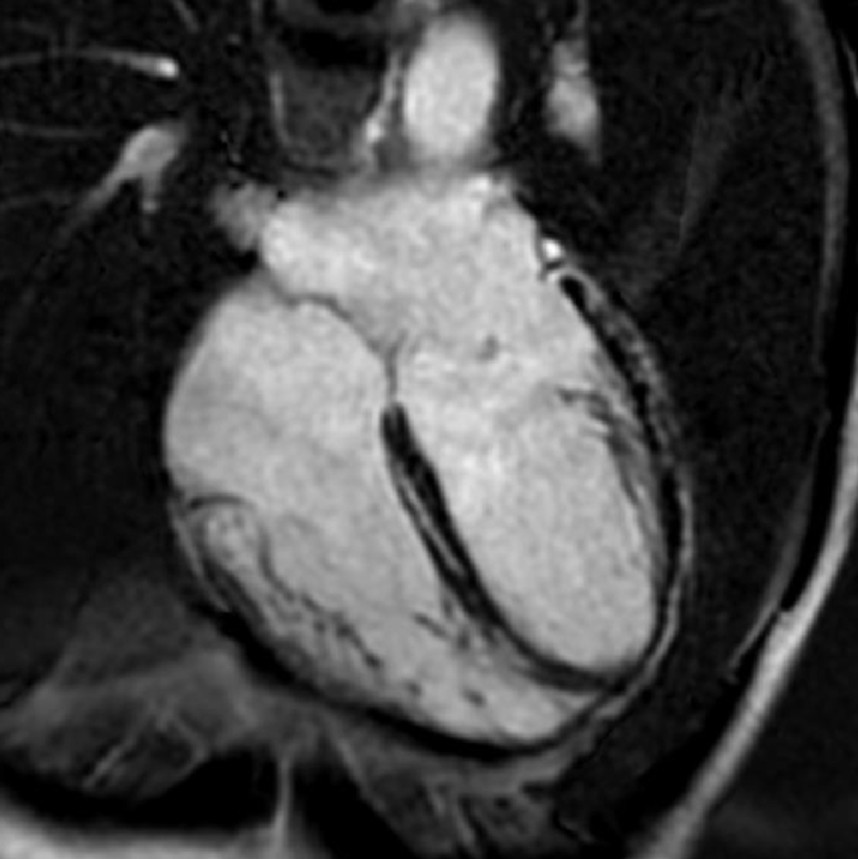

1-Beat Cardiac migliora la qualità diagnostica dell’angio-TC coronarica

L’angio-TC coronarica (CCTA) è uno strumento diagnostico essenziale per l’identificazione delle malattie coronariche, ma la sua affidabilità può essere compromessa nei pazienti con frequenza cardiaca elevata. Grazie ai progressi tecnologici, la modalità 1-Beat Cardiac consente ora di ottenere immagini di alta qualità anche in condizioni di elevata frequenza cardiaca.